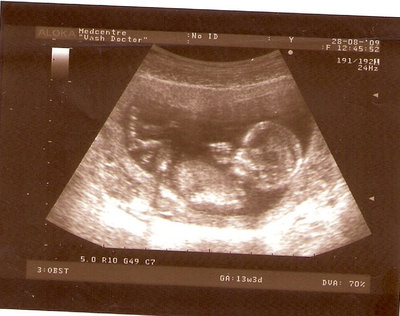

13 НЕД И 5 ДНЕЙ

| Вложения: |

3.jpg [ 96.81 КБ | Просмотров: 2447 ]

Nikisa писал(а): Foto prosto chudesnoe. A na kakom sroke uznali, chto sin.............. НА 13 НЕДЕЛЯХ.КАК РАЗ ВОТ В ЭТО узи, ОНО УМЕНЯ ВТОРОЕ БЫЛО. ЭТО КОНЕЧНО МАЛЕНЬКИЙ СРОК ДЛЯ ОПРЕДЕЛЕНИЯ ПОЛА. НО Я ПОПРОСИЛА ВРАЧА(ЭТО КТСТАТИВ РОССИИ БЫЛО) ХОТЯ БЫ ПРЕДПОЛОЖИТЬ. ЕЙ ВСЁ ТАКИ УДАЛОСЬ РАССМОТРЕТЬ.НУ ВООБЩЕМ ЧЕРЕЗ НЕСКОЛЬ ДНЕЙ ПОЙДУ К ВРАЧУ, УЖЕ АМЕРЕКАНСКОМУ И УЗНАЮ ТОЧНО. К ТОМУ ВРЕМЕНИ У МЕНЯ БУДЕТ СРОК 18 НЕДЕЛЬ. ХОТЕЛОСЬ БЫ ПОСМОТРЕТЬ НА ДРУГИЕ ФОТО НА ЭТОМ СРОКЕ ИЛИ БОЛЬШЕ. ТАК ЧТО ВЫКЛАДЫВАЙТЕ, ЕСЛИ НЕ ЖАЛКО!